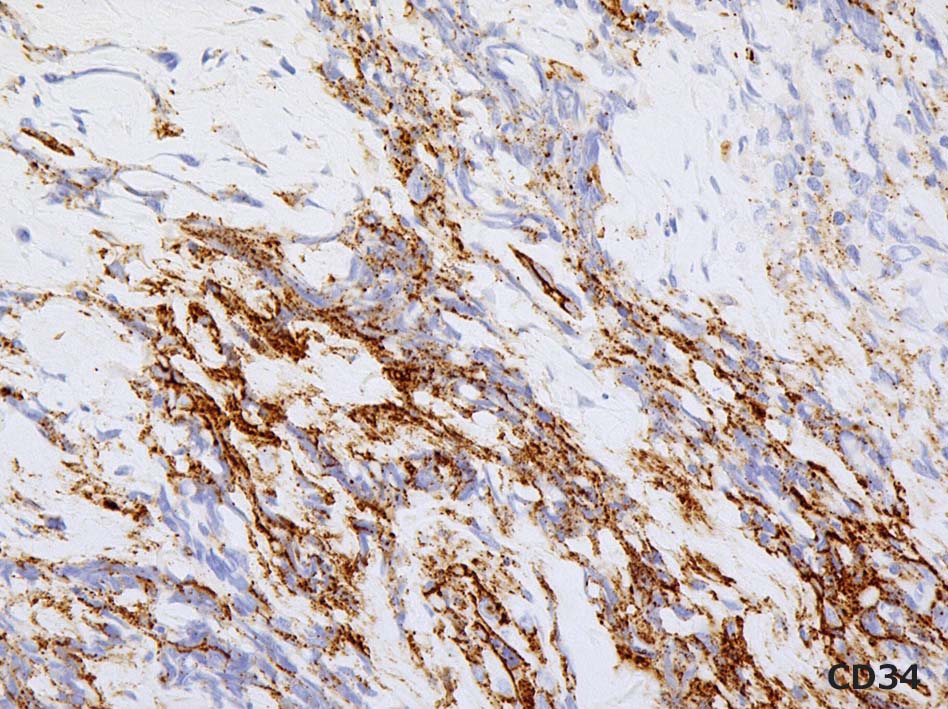

Vimentin, CD99(MIC2)はびまん性に陽性を示す. CD34はfocalに陽性. 異型 spindle cellにも陽性を呈する. EMAは少数の陽性細胞あり. BCL2はリンパ球に陽性. 腫瘍細胞はほぼ陰性. 淡く染まる細胞がごく少数ある. CK(AE1/3)は陰性. p53はびまん性, 80%に陽性. (photo準備中). MIB-1 LIは>90%.

BRG1は核染色性が消失. internal controlの血管内皮や炎症細胞は核に陽性となる. INI1(SNF5/SMARCAB1)はびまん性に陽性. p53が多くの腫瘍細胞に陽性となる.